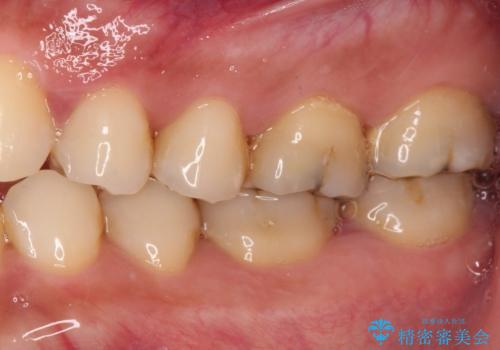

奥歯の歯間部の歯肉が炎症で赤黒くなっており、歯周ポケットを検査したところ、6-8mm(正常では3mm以下)であり、外科処置が適用となる状態でした。

まずは仮歯に置き換え、歯周ポケットを除去するための外科処置(歯肉弁根尖側移動術)を行い、治癒を待ってセラミッククラウンにて補綴治療を行うこととしました。

外科処置後は知覚過敏症状が酷くなることが多いのですが、術後は比較的落ち着いており、スムーズに処置を進めることができました。